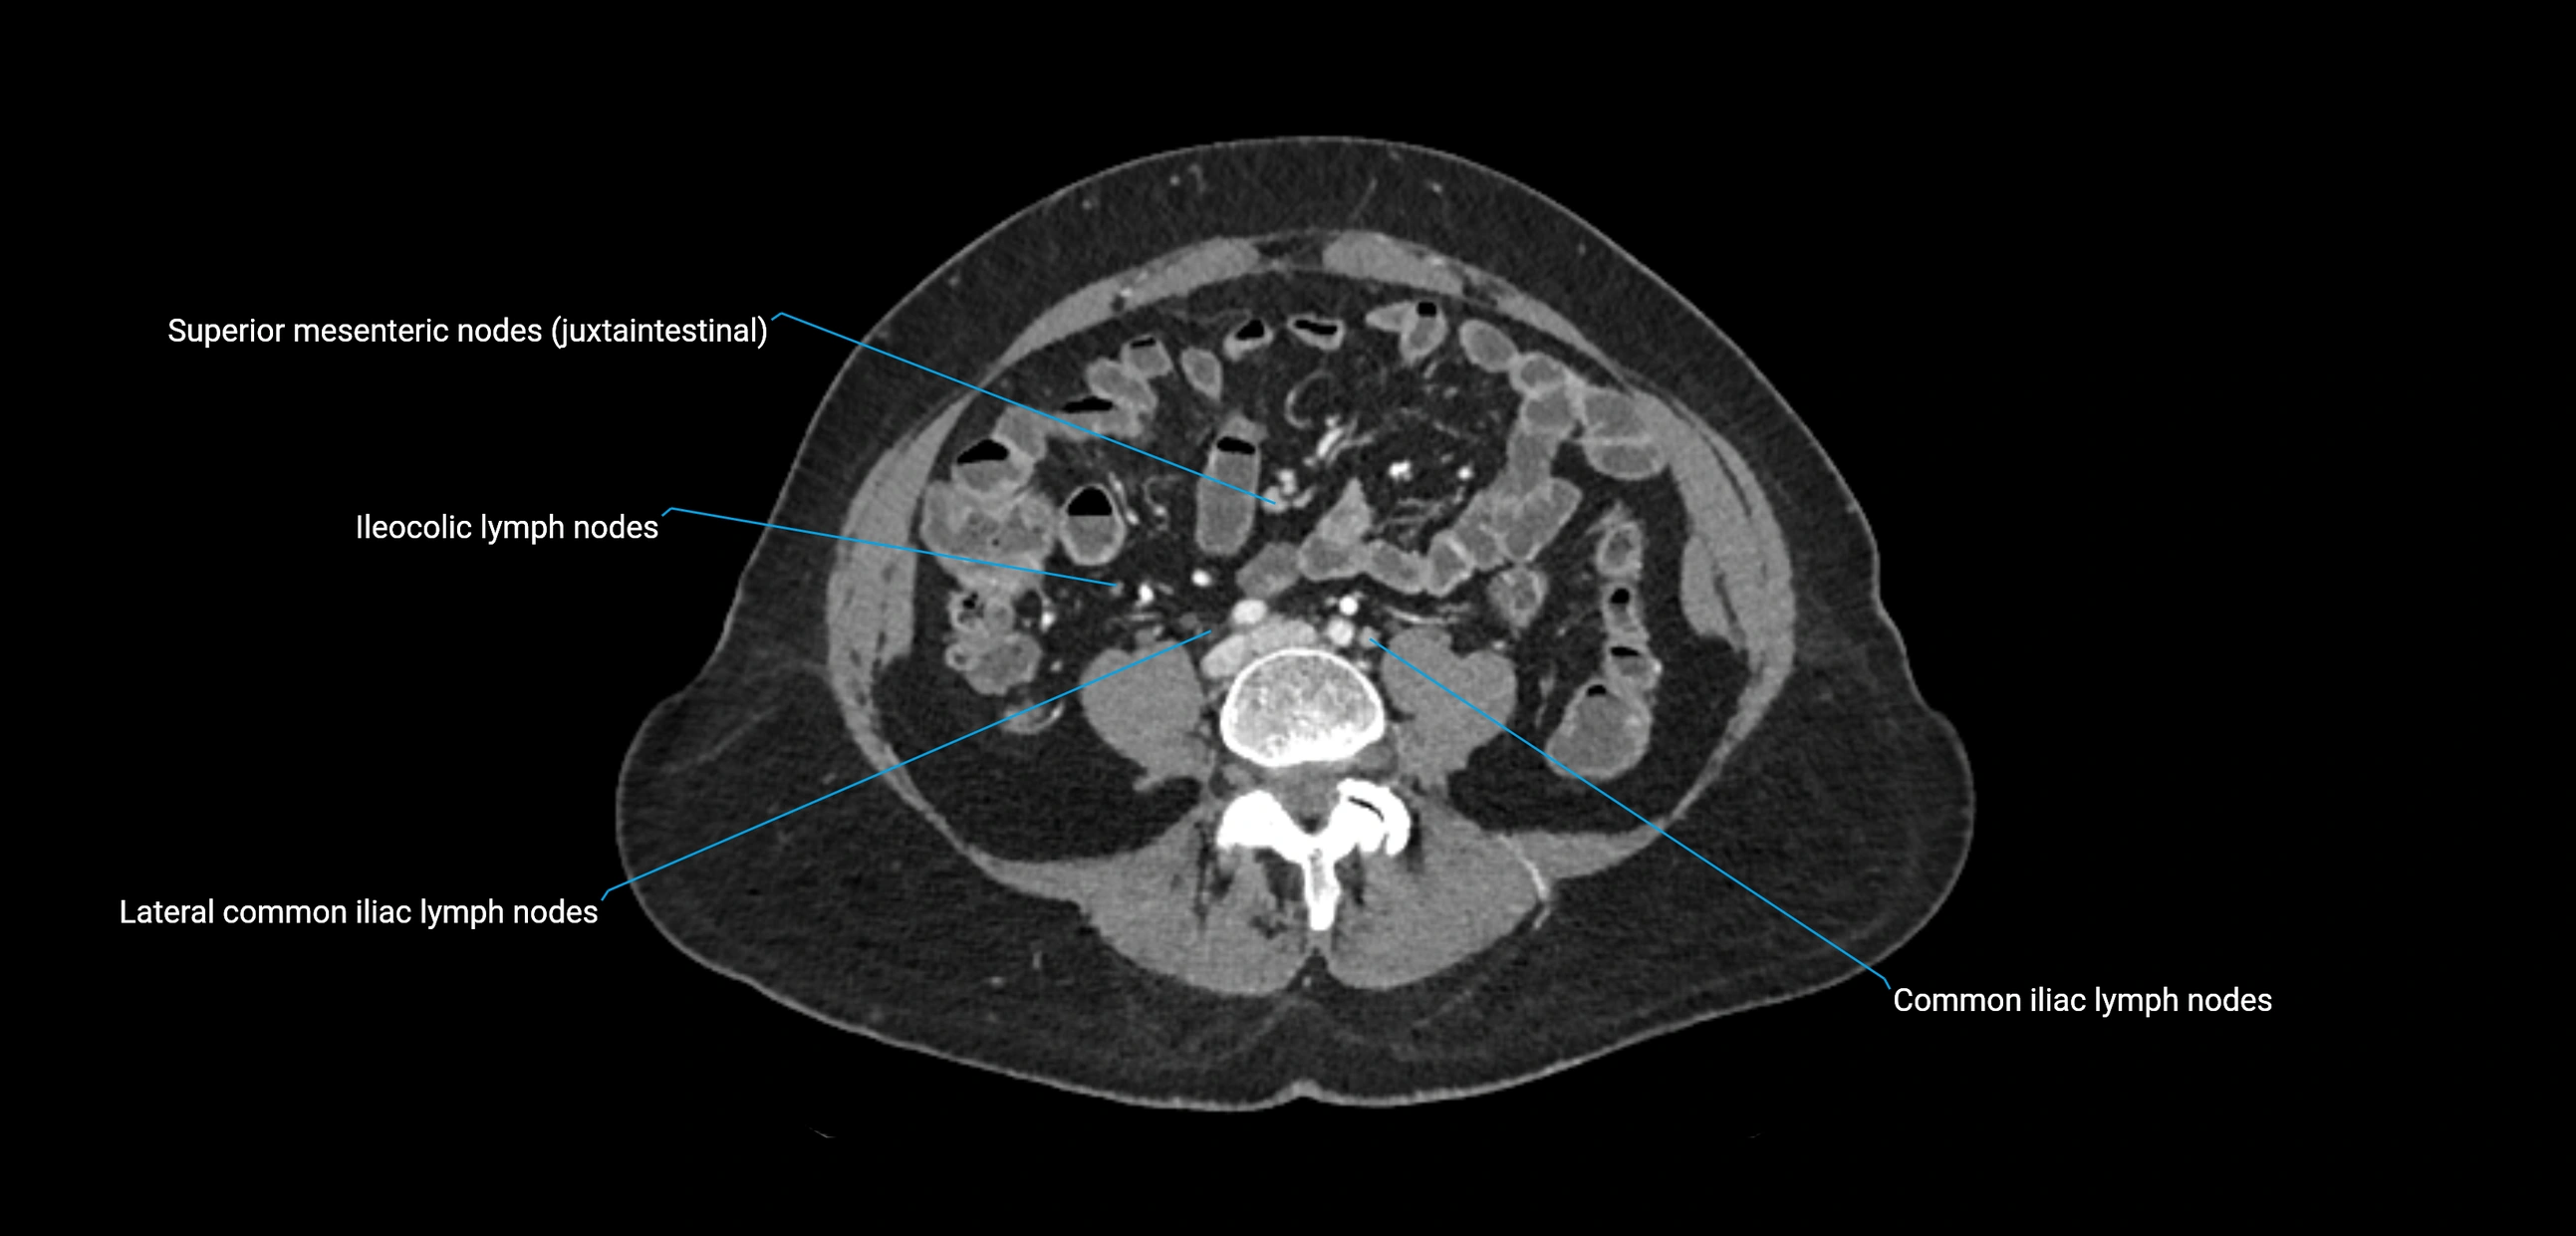

CT Appearance

CT Pre-Contrast:

• Nodes appear as soft-tissue density nodules adjacent to the aorta and IVC

• Calcification may be seen in chronic infections (e.g., tuberculosis)

CT Post-Contrast:

• Normal nodes enhance homogeneously

• Malignant nodes may show heterogeneous enhancement, central necrosis, or conglomerate formation

• Size >1 cm short axis is suspicious, though morphology and distribution are equally important